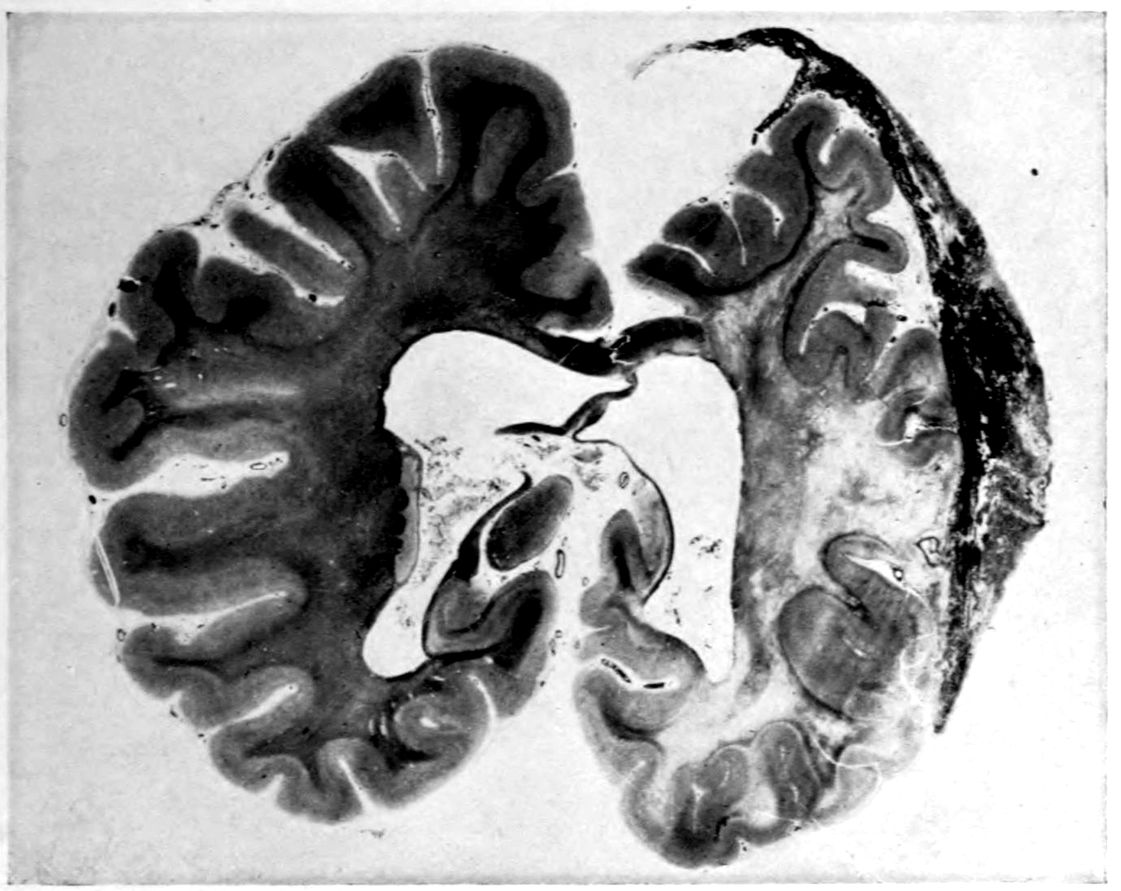

Case I. Spinal Cord (Three Levels) Showing:

A. Marginal sclerosis—effect of old meningitis now extinct.

B. Posterior column sclerosis—effect of meningitis about posterior roots also now extinct.

C. Bilateral pyramidal tract sclerosis—effect of cerebral thrombotic lesions.

Note distortion of tissues in B and C, partly artificial (tissues in places diffluent).